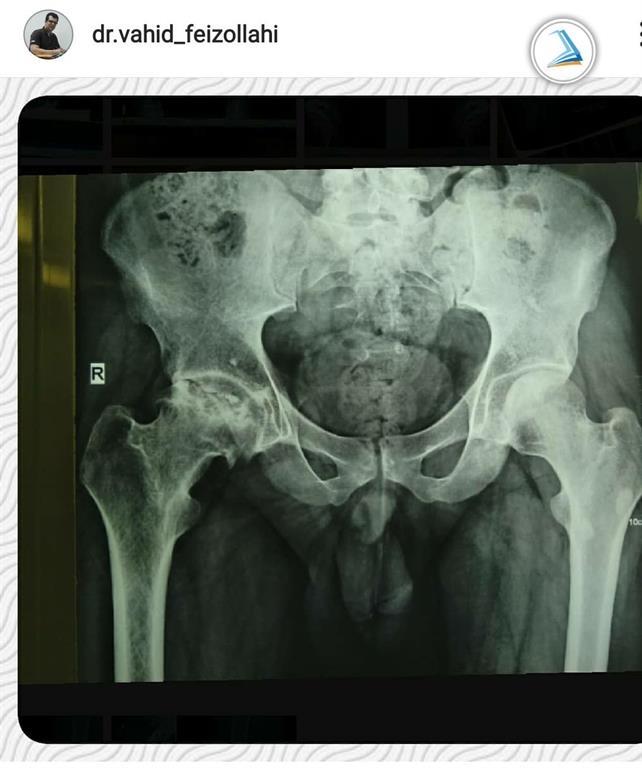

2. A 33-year-old man

A 33-year-old man with femoral head osteonecrosis that lead to limited hip range of motion and severe pain while walking and standing was treated with complete hip replacement surgery and was launched on the day after the surgery.